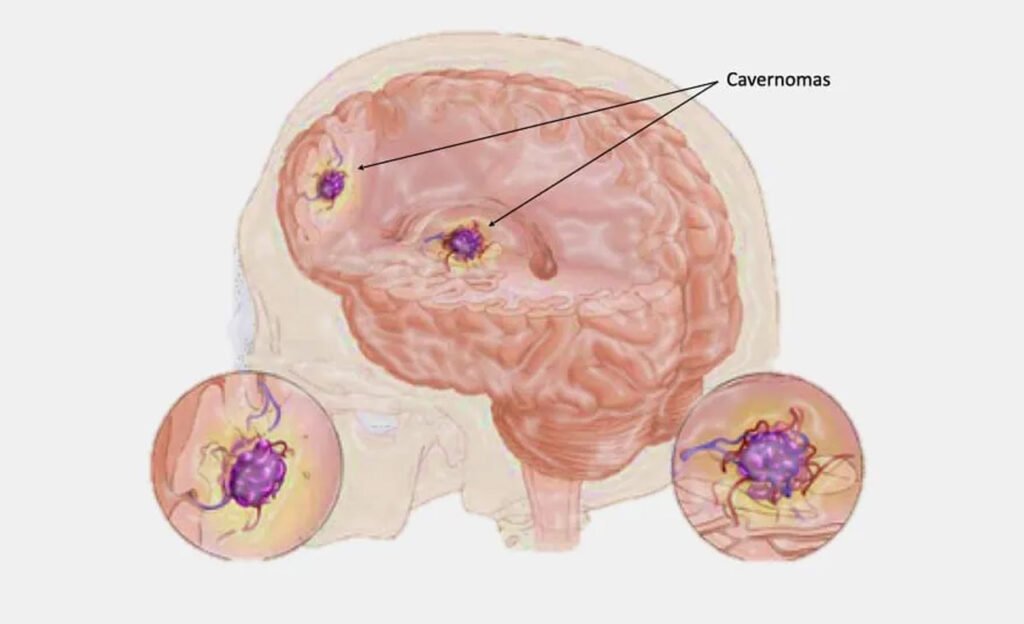

Cavernomas

O que é um cavernoma? Os cavernomas, também conhecidos como malformações cavernosas ou angiomas cavernosos, são lesões vasculares benignas formadas por aglomerados de capilares dilatados e […]